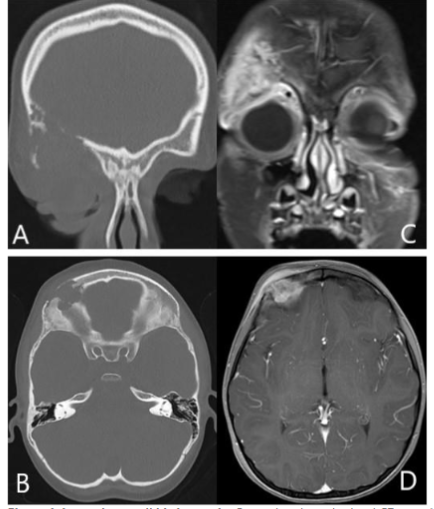

An orbital CT scan showed severe right orbital proptosis, right-sided pre- and post-septal soft tissue thickening with intraconal/retrobulbar space extension and diffuse thickening of the adjacent bone secondary to chronic inflammation without erosion. There was also diffuse paranasal sinus mucosal thickening.

Orbital MRI provided a clearer characterization of diffuse retro-orbital soft tissue thickening, involving the fat, extraocular muscles, and lacrimal glands, leading to pronounced right orbital proptosis and globe eversion. The right globe was flattened with optic nerve stretching. The retrobulbar mass extended posteriorly into the orbital apex without cavernous sinus involvement, and there was also further extension into the lateral face, affecting the temporalis muscle.

FDG PET/MRI was used to characterize the extent of the disease and determine the optimal site for tissue biopsy. FDG PET/MRI revealed multiple markedly FDG-avid cervical lymph nodes, focal intense uptake in the right parotid region, and focal uptake in the right orbital infiltrative mass with maximum Standardized Uptake Value (SUV) of 13. Guided by FDG PET/MRI, the patient underwent a biopsy of the most FDG-avid region of the right orbital mass, which was diagnosed as necrobiotic xanthogranuloma with increased IgG4 expression. The patient was treated with cyclophosphamide, corticosteroid, and high-dose IVIG followed by bone marrow stem cell transplantation and showed a good response in terms of both imaging and clinical evaluation. The genetic and histopathologic findings of this case are discussed in detail by Guess et al.